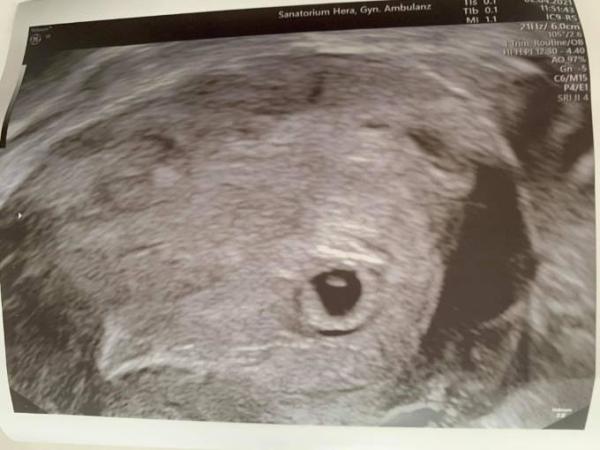

Hallo, Ich hatte eben meinen ersten Frauenarzttermin. Ich habe einen sehr langen Zyklus, der aber durch das Absetzen der Pille nicht regelmäßig kommt. Mein Frauenarzt geht von einem normalen Zyklus aus und hat gesagt, dass ich 6+0 sei. Ich habe aber Ovulationstest gemacht. Demnach bin ich aber gerade erst am Anfang der 6. SSW (maximal 5+2) Heute auf dem Ultraschall hat man eine leere Fruchthöhle gesehen und den eventuellen Ansatz eines Fruchtsacks. Der Frauenarzt hat mir Angst gemacht. Muss ich mir sehr große Sorgen machen?

Unglaublich, wie unempathisch und auch inkompetent manche Ärzte sind. Mach dir mal keine Sorgen. Da du ja selber den Eisprung bestimmt hast, solltest du auch von deinen Berechnungen ausgehen. Und für 5+2 sieht alles super aus auf deinem Ultraschallbild. Überhaupt kein Grund sich Sorgen zu machen. Dass man die Fruchthöhle bereits in der Gebärmutter, plus einem Ansatz von einem Dottersack, erkennt ist schonmal viel Wert. Entspannt dich, alles gut!

Für 5+2 sieht Deine Fruchthöhle aber ganzschön groß aus. Sieht eher weiter aus als 5+2... durch deinen Ovulationstest weißt du trotzdem nicht, wann dein Eisprung war. Die Schwangerschaftswoche wird nun Mal anhand der Fruchthöhle/ Embryo berechnet also vergiss das erstmal mit deinen Ovus.

Hey, Danke für deine schnelle Antwort. Die Fruchthöhle ist auf dem Bild sehr stark vergrößert. Er hat zuerst 8mm gemessen, aus einem anderen dann 9mm. Ich bin einfach total verunsichert.

Wenn deine Fh bereits 8mm groß ist, Dann bist Du auf keinen Fall erst 5+2 Bleibe einfach entspannt. Bei deinem nächsten Termin sieht man auf jeden Fall das Herzchen schlagen.